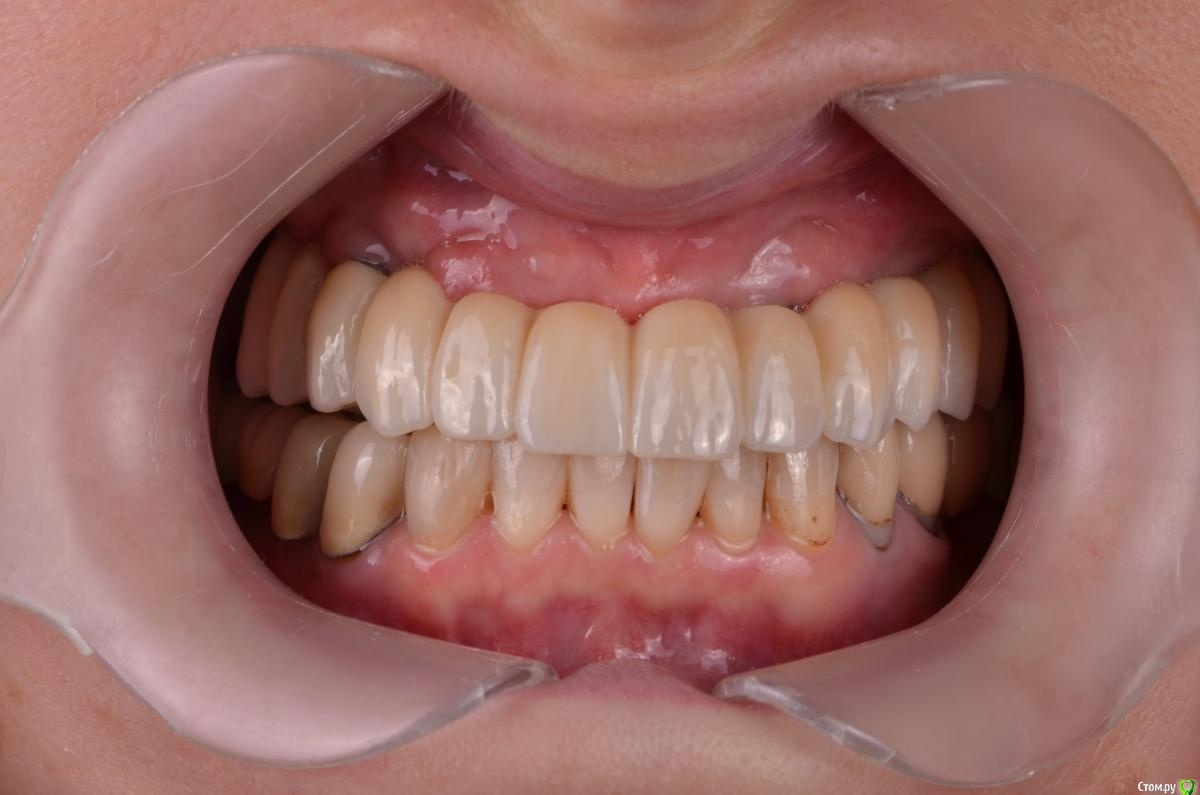

chervoncevdaniil Опубликовано 10 ноября, 2020 Поделиться Опубликовано 10 ноября, 2020 (изменено) Коллеги,есть пациент,внизу стоят коронки,установленные лет двадцать назад,пациент менять не хочет. На верху стоят 4 импланта,от съемного категорический отказ(неудачный опыт)Обсудили вариант с несъемной конструкцией с укороченным зубным рядом.(10 зубов)Вопросов несколько,какой материал бы вы предложили,и что по длинне консоли для этой конструкции. P.S.Винтовой фиксации тут не будет,импланты установлены нет под оптимальными углами. Я рассматриваю 3 варианта:1)Циркон в полную анатомию на индивидуальных абатментах с наддесневым уступом+небольшие консоли2)Мк на титановых премилах+небольшие консоли3)Циркон в полную анатомию с титановой балкаой и консоли(такие конгструкции не разу не делал)Акрил не хочу,потому что внизу мк коронкуЯ конечно,больше всего к первому варианту склоняюсь,но знаю что на циркониевых больших работах могут быть проблемы с трещинами.В общем,жду ваших советов/рекомендаци Изменено 10 ноября, 2020 пользователем chervoncevdaniil Ссылка на комментарий

chervoncevdaniil Опубликовано 12 ноября, 2020 Автор Поделиться Опубликовано 12 ноября, 2020 (изменено) Коллеги,спасибо всем за советы,напишу свои выводы.Я честно говоря,изначально побаивался цельный циркон без балки не по причине сколов,а по причине трещин каркаса,что периодически на таких подковах может случаться,поэтому с этой стороны я больше склонялся к мк,но в случае с мк встречными с его старыми коронками я как раз боюсь за сколы,а они возможны,потому что причина замены протеза на локаторах постоянные агрессивные и очень быстрые износы матриц.Варианты с культями идеальны,но мы в бюджет не пройдем да и честно говоря не уверен что лаборатория сможет исполнить как надо.Сейчас склоняюсь больше все таки к тому,чтобы выточить из максимально прочного циркона в полную анатомию с толстенными коннекторами Изменено 12 ноября, 2020 пользователем chervoncevdaniil Ссылка на комментарий